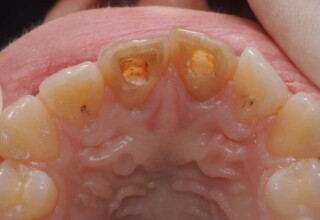

Δύσχρωμα απονευρωμένα δόντια

Μια ιδιαίτερη περίπτωση δύσχρωμων απονευρωμένων δοντιών που ο κεντρικός είχε βλάβη από εξωτερική απορρόφηση. Έγινε καθαρισμός του κεντρικού από την βλάβη και επειδή δεν μπορούσε να λευκανθεί λόγω της επαφής με τα ούλα, σφραγίστηκε σε πρώτη φάση, μετά λευκάνθηκε και στο τέλος έγινε η τελική αποκατάσταση.

Αρχική εμφάνιση

Τελική εμφάνιση